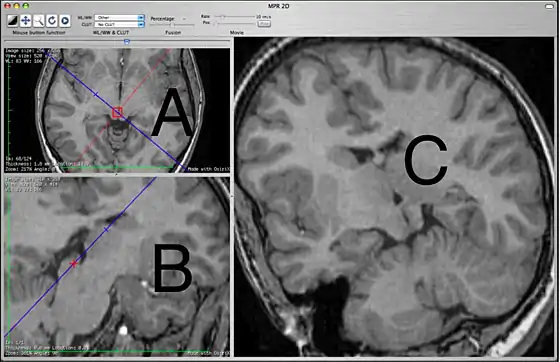

The 2D MPR window

This 2D MPR Viewer allows generating a MPR slice in any position and orientation through the 3D volume. This mode shows three viewing ports. In the picture above, the two on the left are labeled A and B. The third, on the right, is labeled C.

The primary purpose of the A and B view ports is to specify the plane that will be shown in the C view port. The A and B view ports are partially obscured by lines used specify the plane to be seen in C. These lines cannot be hidden. In this sense, the C view port is designed for diagnostic viewing and the other two view ports are primarily to specify what is to be shown in C. The view ports are not all equal, which may be different from what users of other MPR interfaces are expecting. View port A shows a blue line which corresponds to the orientation of what is being seen in C and also contains a red line that corresponds to what is seen in B. View port B shows only a blue line that also corresponds to what is seen in C. View port C has no lines.

The specifying view port A will show the original images in the plane that they were originally acquired, most commonly the axial plane. You can scroll through these images to choose the one that you want to work off. The specifying view port B shows planes that are orthogonal to view port A. If A is showing an axial image then on initially opening the 2D MPR Viewer, B will show a sagittal image. The specific orthogonal plane that is being created in B is indicated in the A view port as a red line. Under these initial circumstances, C will be showing a coronal reconstruction that corresponds to the blue line.

If you are interested in seeing a sagittal image, one can simply look at the B view port but this is not really what a specifying view port is for. The specifying view ports are smaller and obscured by lines. To see a clean sagittal image, you want to grab the blue line in view port A and swing it 90 degrees. At this point, the C view port will show a sagittal image. The red line, indicating the plane of view port B, will maintain itself perpendicular to the blue line. This line, indicating the orientation of view port B, will now be documenting the coronal plane that is visible in B. You cannot grab the red line to do this rotation. Only the blue line can be grabbed. You can move the intersection of the two lines by grabbing within the red circle. This will center the point of rotation

Simply by using the A specifying view port, you can show any orthogonal plane between sagittal and coronal in the C diagnostic view port. However, to specify oblique planes requires the simultaneous use of view port B. When you specify an oblique plane, it requires that you look primarily at the blue line in B to understand what plane is being shown in C. It is possible, for example, to have the blue line in A completely outside the body part being shown in A and yet something is still being shown in C. Once you are looking at oblique planes, the blue line in A is of limited value in terms of understanding what you are looking at in C.